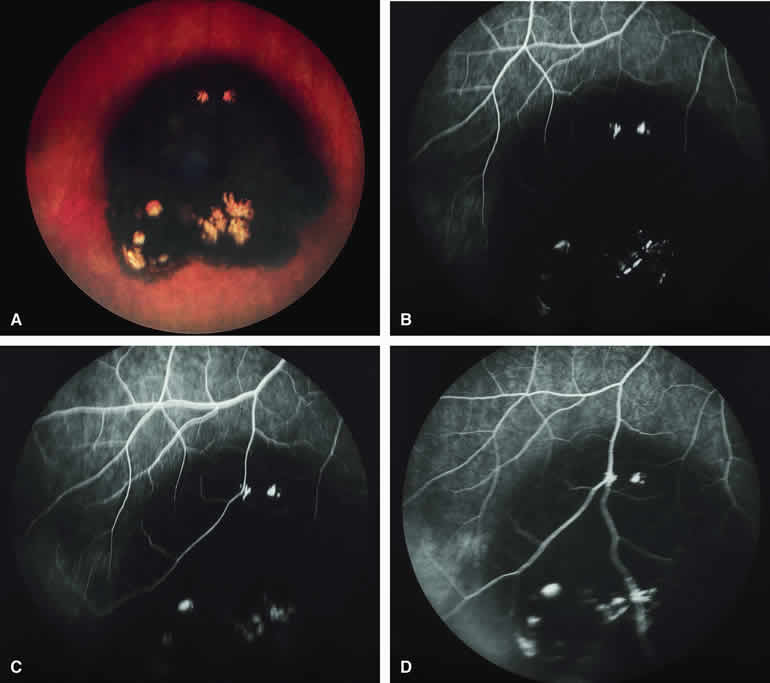

Choroidal Nevus with Drusen and Clumps of RPE Hyperplasia

If a choroidal nevus has drusen and RPE alterations on its surface (see Fig. 4A), fluorescein angiography (Fig. 4B, C, and D) tends to show patchy or stippled window defect hyperfluorescence corresponding to foci of RPE depigmentation, fluorescence blockage by clumps of RPE hyperplasia on the surface of the lesion, and late staining of at least some of the drusen. These features are not usually as evident on ICG angiography as they are on fluorescein angiography.